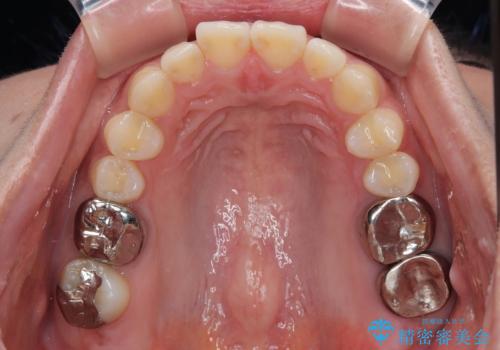

その後、挺出していた右上第一大臼歯と第二大臼歯に装着されていた銀歯についても、審美性と適合性の向上を目的に、オールセラミッククラウンにやり替えました。

これにより、より自然で美しい見た目と、高い精度の咬合が得られています。